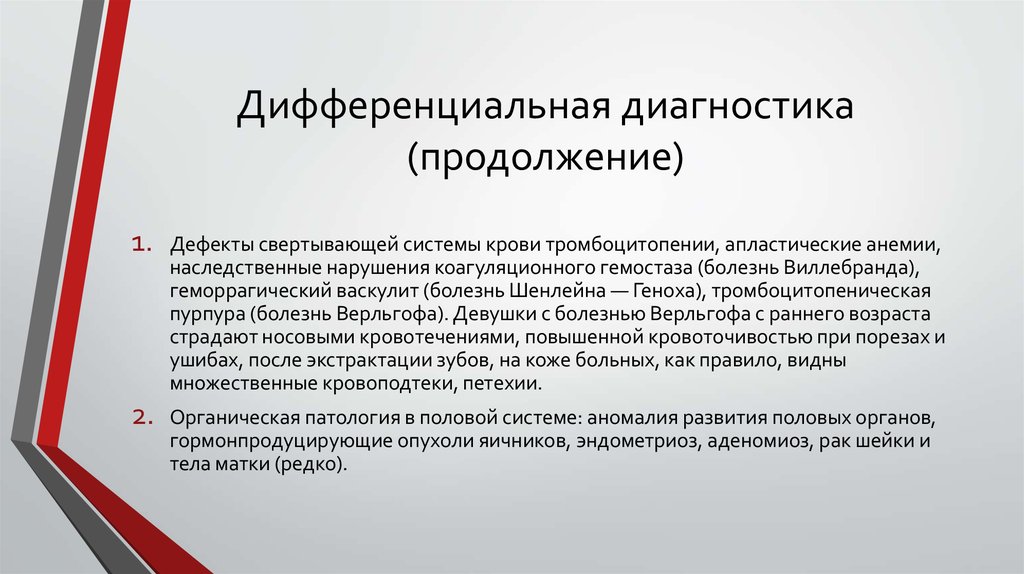

Дифференциальная диагностика заболеваний плевры